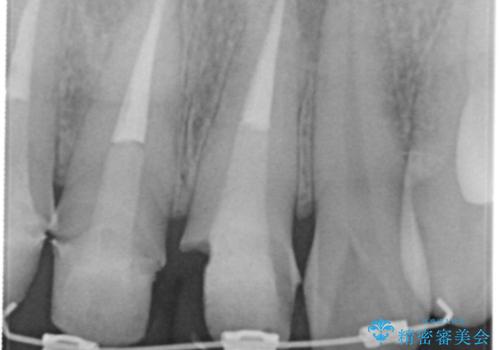

視診・X線検査・歯周組織検査より下記のような問題が列挙され、長期的な予後を見込むために一つづつ問題の解決を計ります。

・不十分な根管治療 →マイクロスコープを用いる精密根管医療

・歯肉縁下カリエス →部分矯正による歯の挺出・歯周外科

歯の挺出を行ったことで歯ぐきの腫れも改善され、安定した歯周環境下でのセラミッククラウン治療を行うことができました。